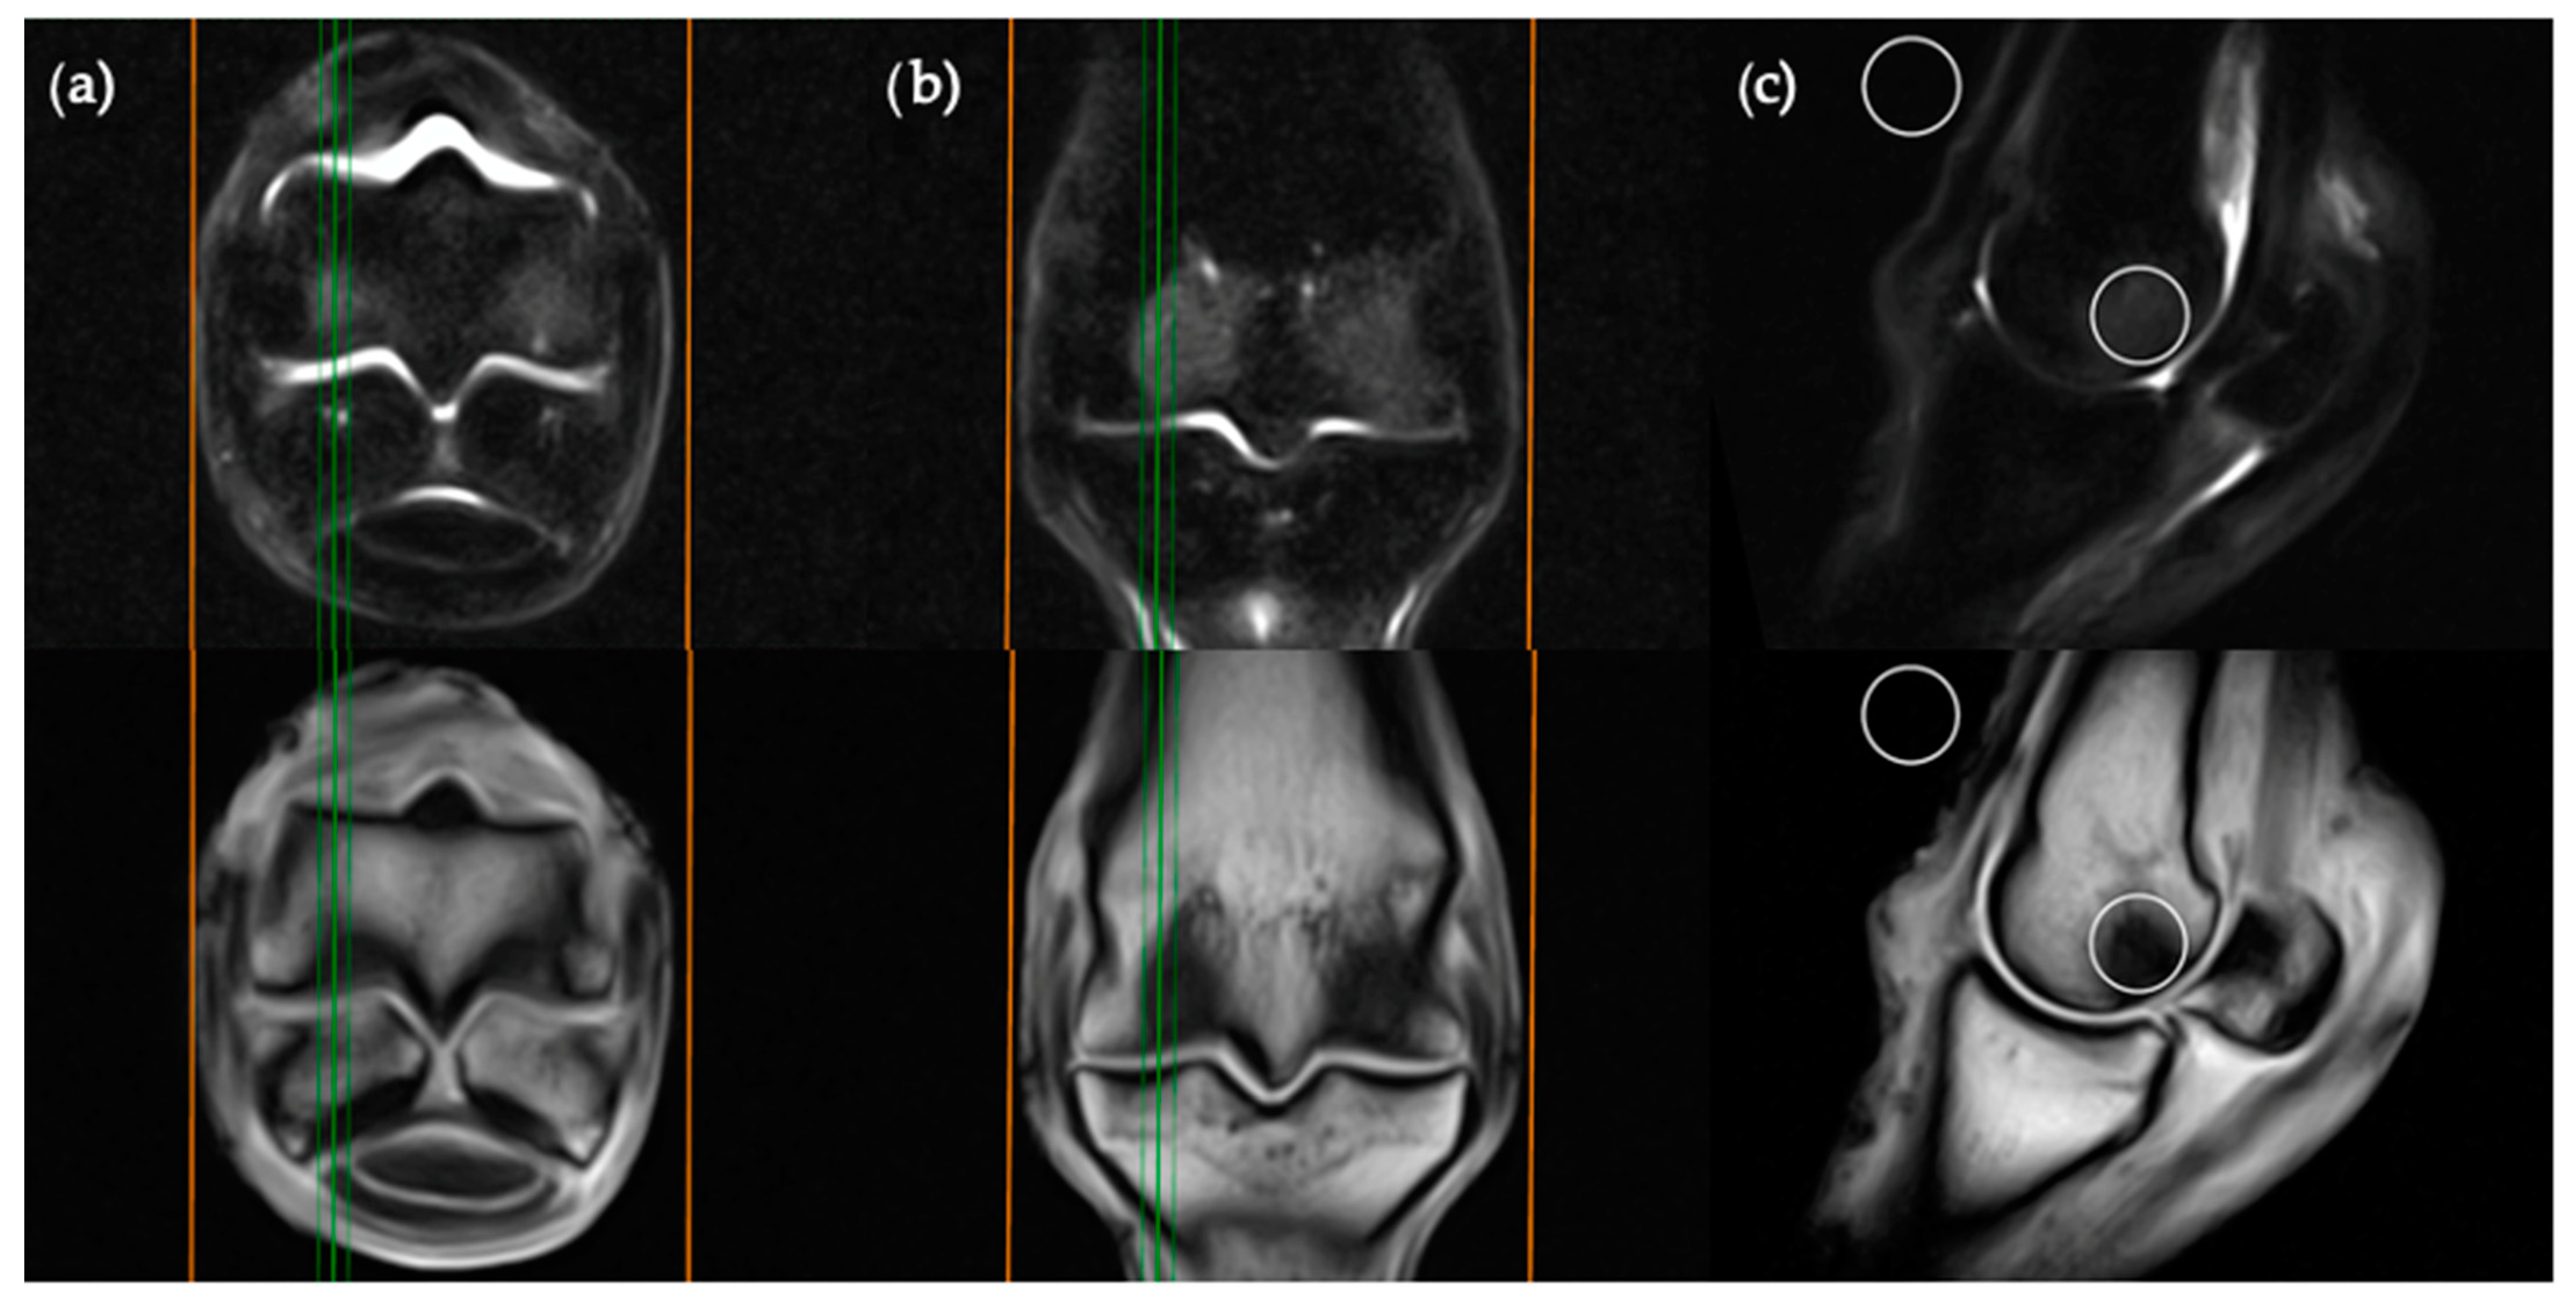

Images were viewed by a veterinary radiologist experienced with the interpretation of low-field equine fetlock MRI examinations (AY). MRI studies were viewed in “digital imaging and communications in medicine” (DICOM) format on an interactive DICOM viewer workstation (Osirix MD). Standardised regions of interest (ROIs) of 2 cm2 were imported into each study. The ROIs were positioned in predetermined locations for each plane of the STIR sequences (Figure 1, Figure 2, Figure 3 and Figure 4) then copied across to the corresponding T1W slice. For every intraosseous ROI measured, a background ROI was also placed external to the anatomy in the same image at a consistent, predetermined location. One to three signal to noise ratios (SNRs) were calculated for each image examined in order to evaluate signal changes between images rather than absolute signal value. SNR is the ratio between the amplitude of the MR signal of a tissue and the standard deviation of the amplitude of the background noise. Use of SNR also allowed for image window and level settings to be adjusted subjectively for each study in order to maximize visualization of intraosseous STIR hyperintensity. Each limb was graded poor, satisfactory, good or excellent for quality of fat suppression in the STIR sequences. The experimental protocol was divided into two parts; blinded and unblinded.

The frontal plane image slice immediately dorsal to the corticomedullary junction of the palmar/plantar cortex of the third metacarpal/metatarsal bone was used to obtain ROI measurements at the distal palmar/plantar aspect of the lateral and medial condyles as well as the axial physis (Figure 1). Condylar ROIs were placed at the edge of the subchondral bone plate within the centre of the lateral and medial condyles. The axial physeal ROI was placed on sagittal midline at the level of the physeal vasculature. The background ROI was placed at the lateral or medial surface of the limb proximal to the epicondyle of the third metacarpal/metatarsal bone.

Figure 1. Short tau inversion recovery (STIR) fast spin echo (FSE) (top row) and T1-weighted (T1W) gradient recalled echo (GRE) (bottom row) MRI images in (a) transverse; (b) frontal and (c) sagittal planes; demonstrating the location of ROI placements in a frontal plane. The green lines on the transverse and sagittal images show the standardized orientation and location of the frontal slice for regions of interest (ROI) placement. The orange lines show the extent and orientation of all the frontal slices acquired in the MRI study.